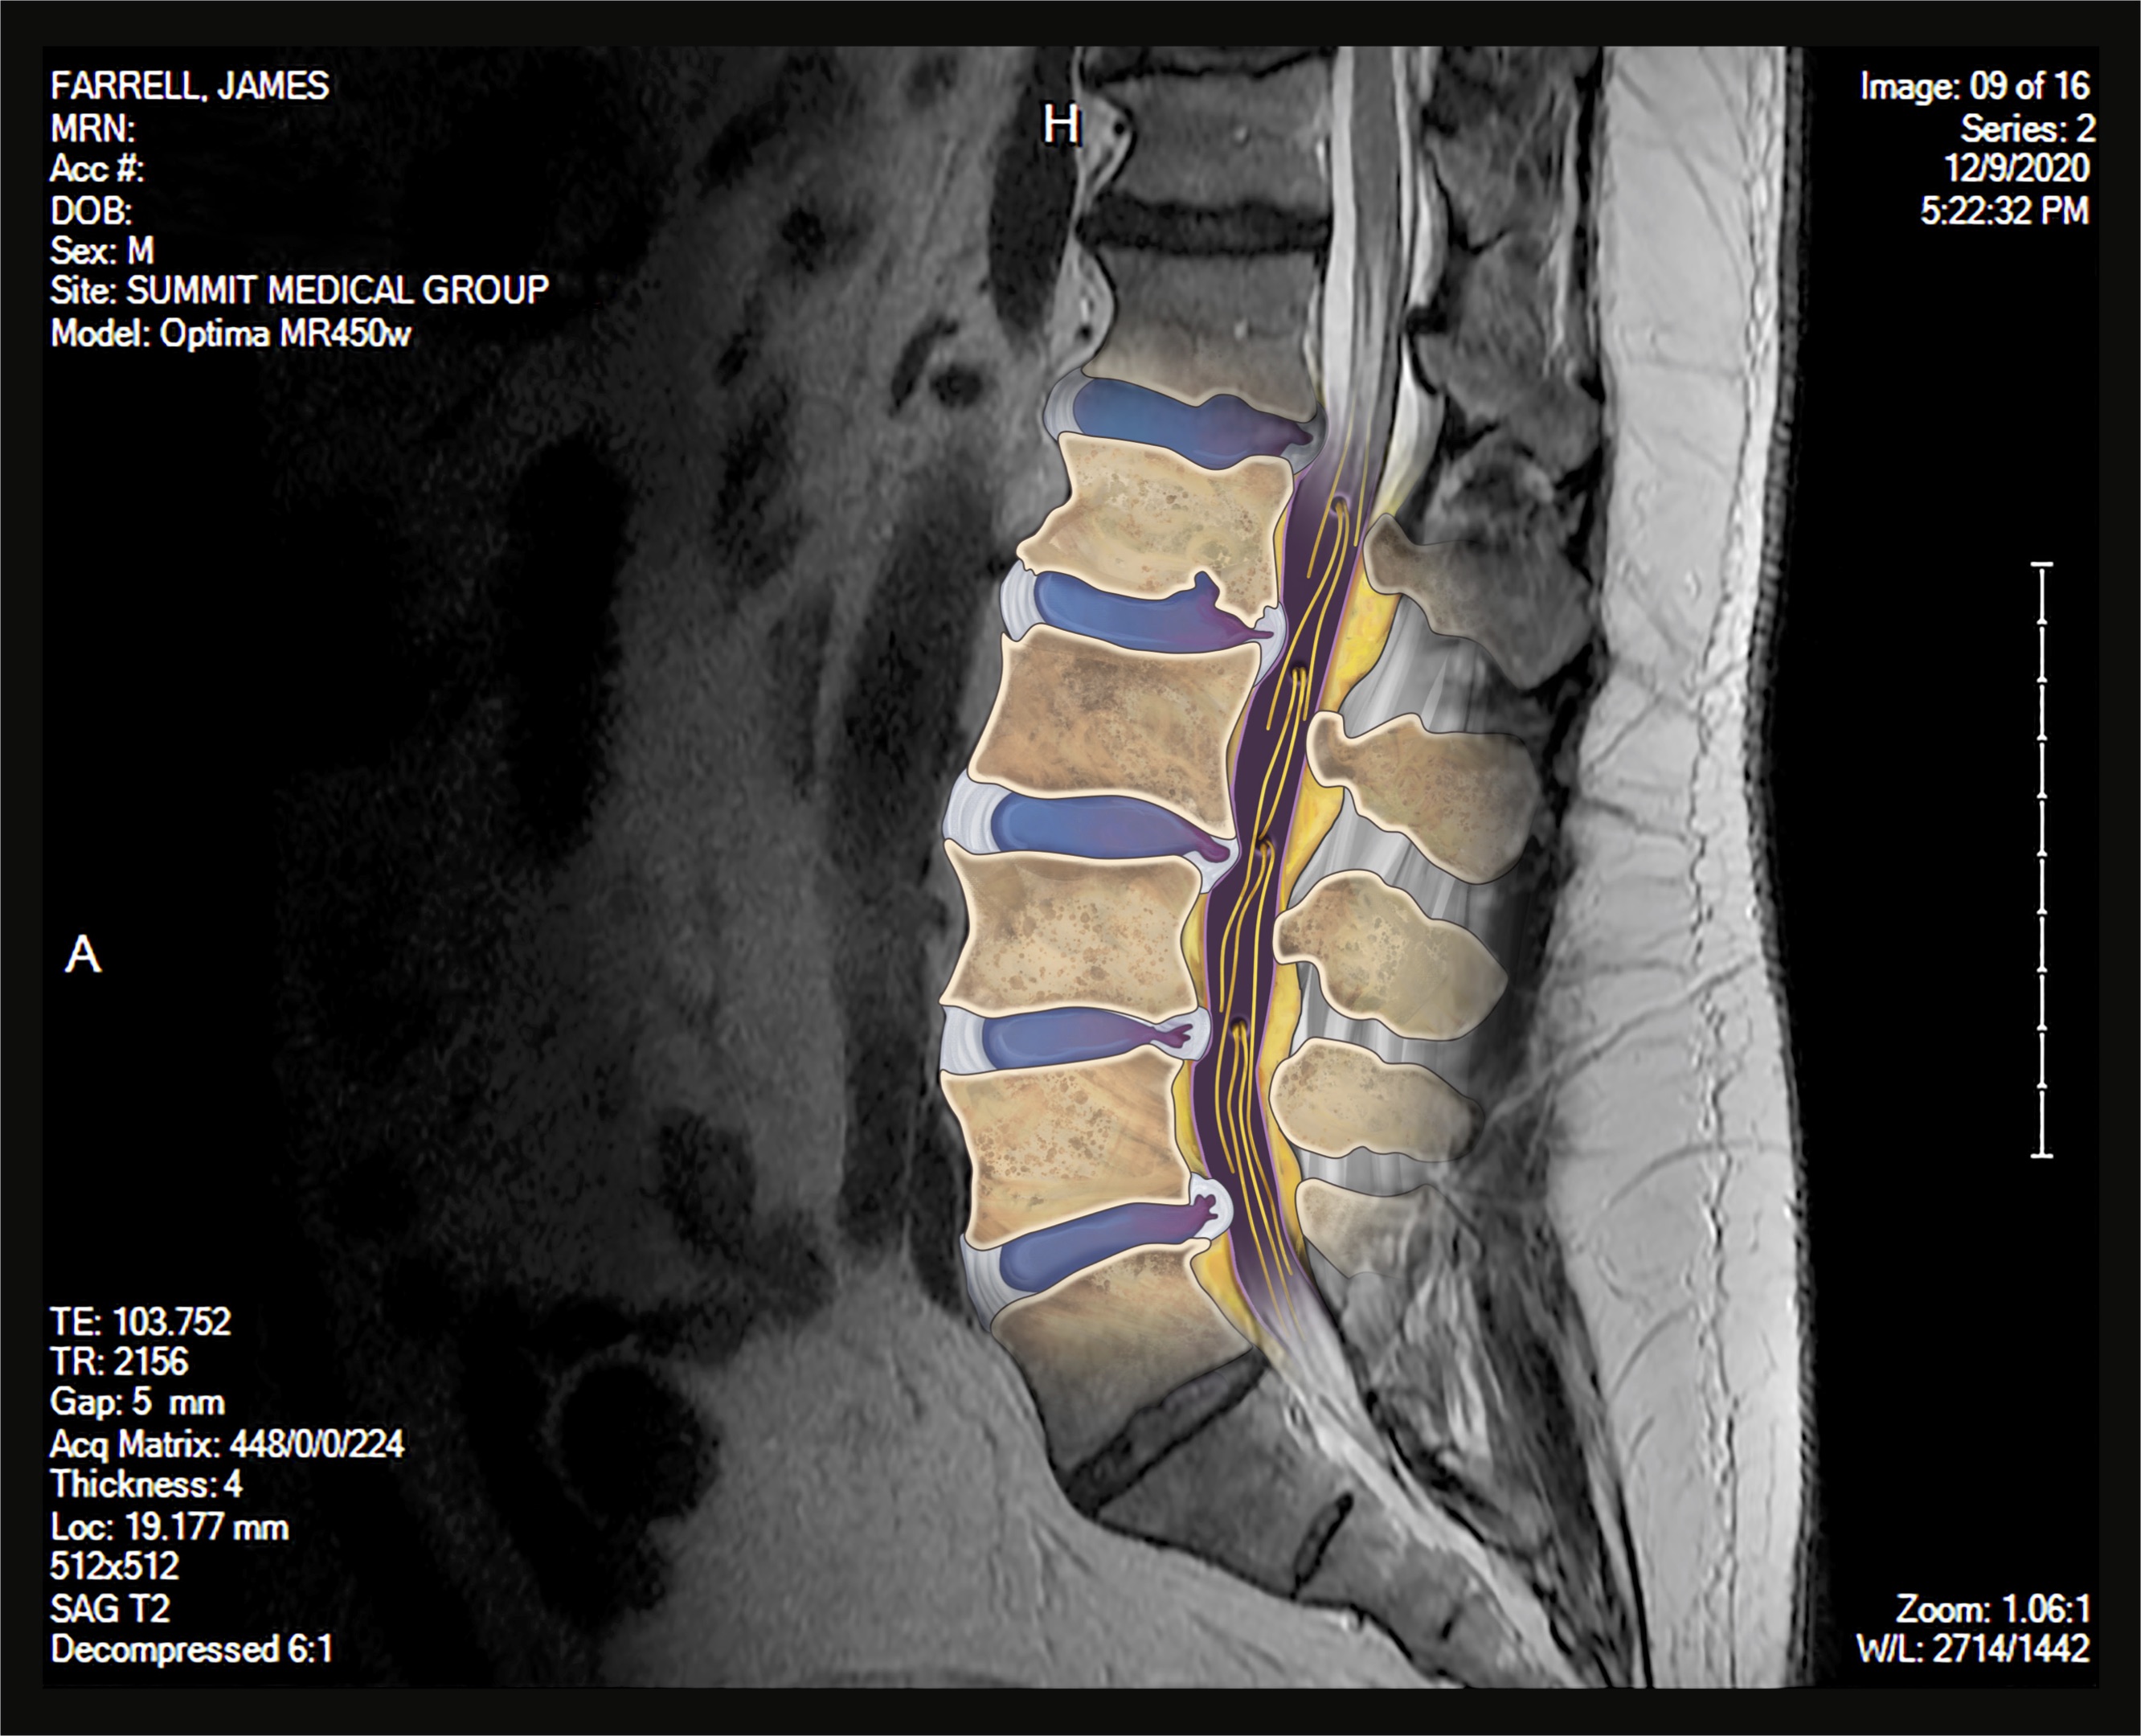

CT scans, MRIs, and X-Rays are all, in a way, portraits of the patient. Films that result from a diagnostic exam display information that is deeply intimate by nature but is often incomprehensible to the patient. The patient learns about themselves and their condition, whether chronic or newly diagnosed, from the words of their physician. Someone without any medical training sees themself as a series of black, white, and gray shapes on a computer screen or printed out on a film. Flesh and bone are abstracted in a way that disconnects them from the body which they represent.

This abstraction and disconnection creates a complicated encounter – how does one relate to an image of themselves when, from their perspective, it looks like little more than television static?

In instances like this where an artist is given a prompt, platform, and permission to create, it is possible to unify select individuals with their films. A patient is elevated to an individual human being by linking a face, name, and snippets of their personality with what would otherwise be a diagnostic assessment reserved for the eyes of physicians. This exhibition is about connecting the individual to themselves and others, and furthering the integration of art and science. Disclosure aims to dignify a patient and their condition through a work of art, and bridge the gap between the results of a diagnostic medical exam and what makes us human.